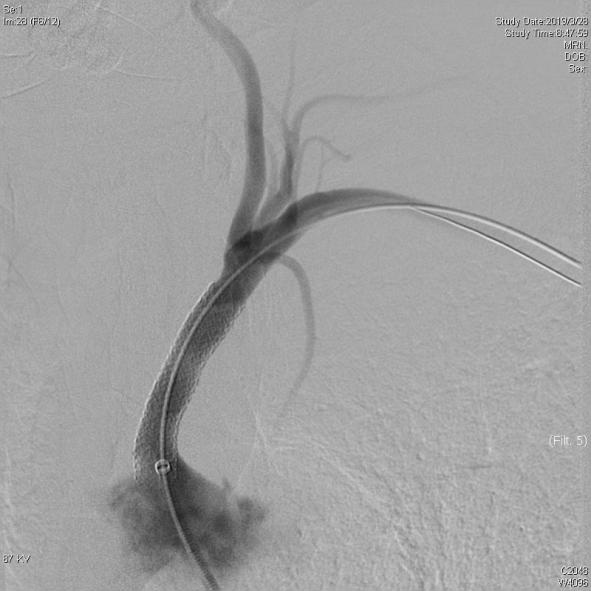

图1左侧锁骨下动脉闭塞,箭头所指               图2 经右侧椎动脉造影:可见血流自左侧椎动脉向远

端逆向供应左侧锁骨下动脉,颅内大脑后动脉显影不佳